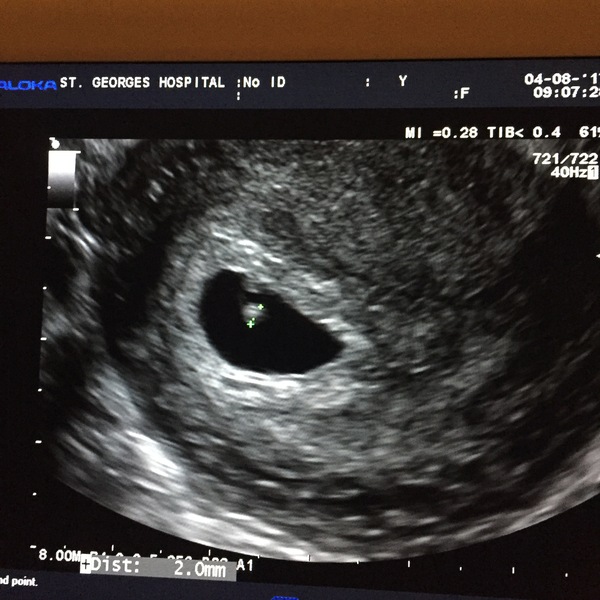

Bumpkin21 · 04/08/2017 18:49

Please may I join as a late comer?

I thought I was 6+2 but had early scan today because of some bleeding and they said I'm 5+3, so due April 3rd, first bubba.

What a cute little scan Flowers

Lovely scan picture Bumpkin.